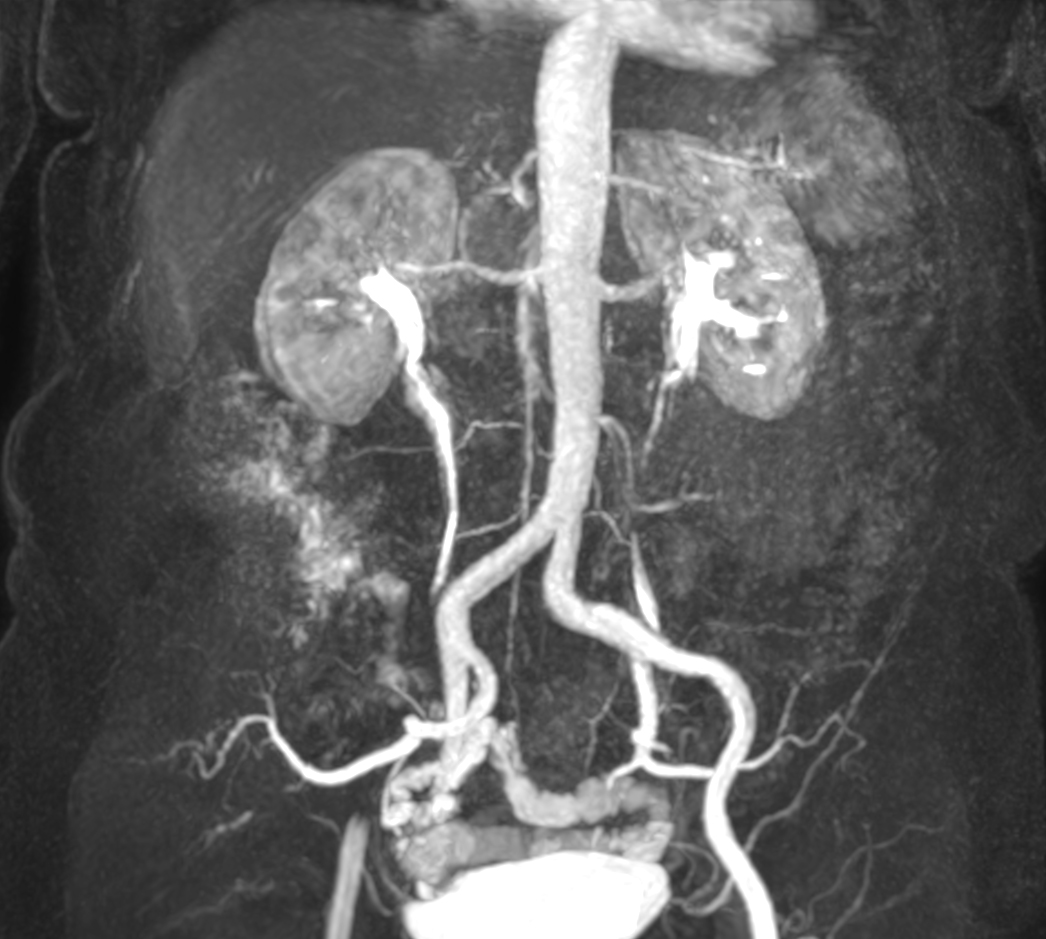

Patient with a known stent in the abdominal veins. Subtraction-less mDIXON MRA run-off is performed using a combination of Compressed SENSE and enhanced gradient strength to increase both in-plane and through-plane spatial resolution. The station covering the feet has been rescanned with a Compressed SENSE factor of 14, resulting in a time resolved scan with a dynamic time of only 4 seconds.

mDIXON MRA (MIP) - Abdomen